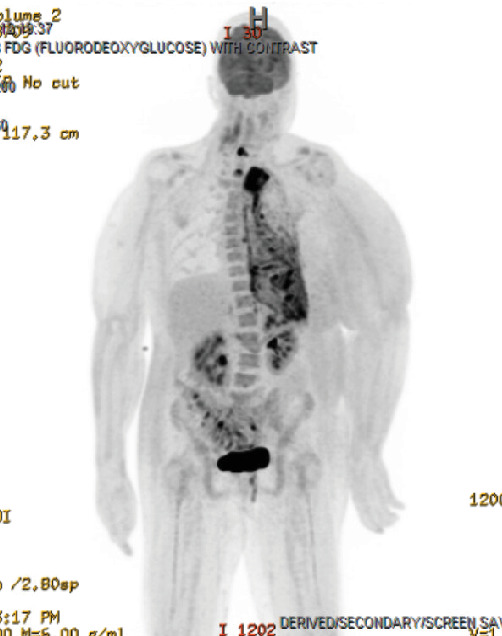

Epithelioid hemangioendothelioma (EHE) is an extremely rare vascular sarcoma that can initially present with a myriad of symptoms anywhere in the body. Imaging findings are often nonspecific, and the pathology tends to have overlap with other malignancies. As a result, it can be quite difficult to suspect and diagnose EHE. We present a case of pulmonary EHE in a 41-year-old female with left pleural thickening and subclavian tumor thrombus who was initially misdiagnosed and treated as mesothelioma. This instance demonstrates the importance of maintaining a broad differential and the utilization of repeat biopsies and next-generation sequencing for questionable diagnoses of atypical malignancies.

Abstract Image